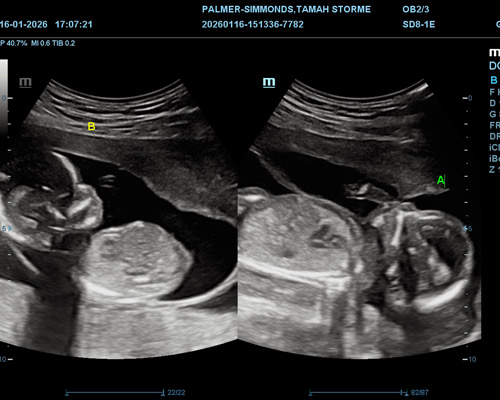

A twin pregnancy scan near Huddersfield allows both babies to be carefully assessed during the same appointment. Because there are two babies to observe, the scan is carried out with additional care to ensure each one is clearly seen and monitored.

During the scan, the sonographer will check important aspects such as both babies’ presence, their heartbeats, positioning, and general development. Watching them move side by side on the screen can be both reassuring and memorable.

Gender identification for twins is usually possible from around 15 weeks onwards. At this stage, both babies are typically developed enough for the sonographer to determine their genders, depending on their position.